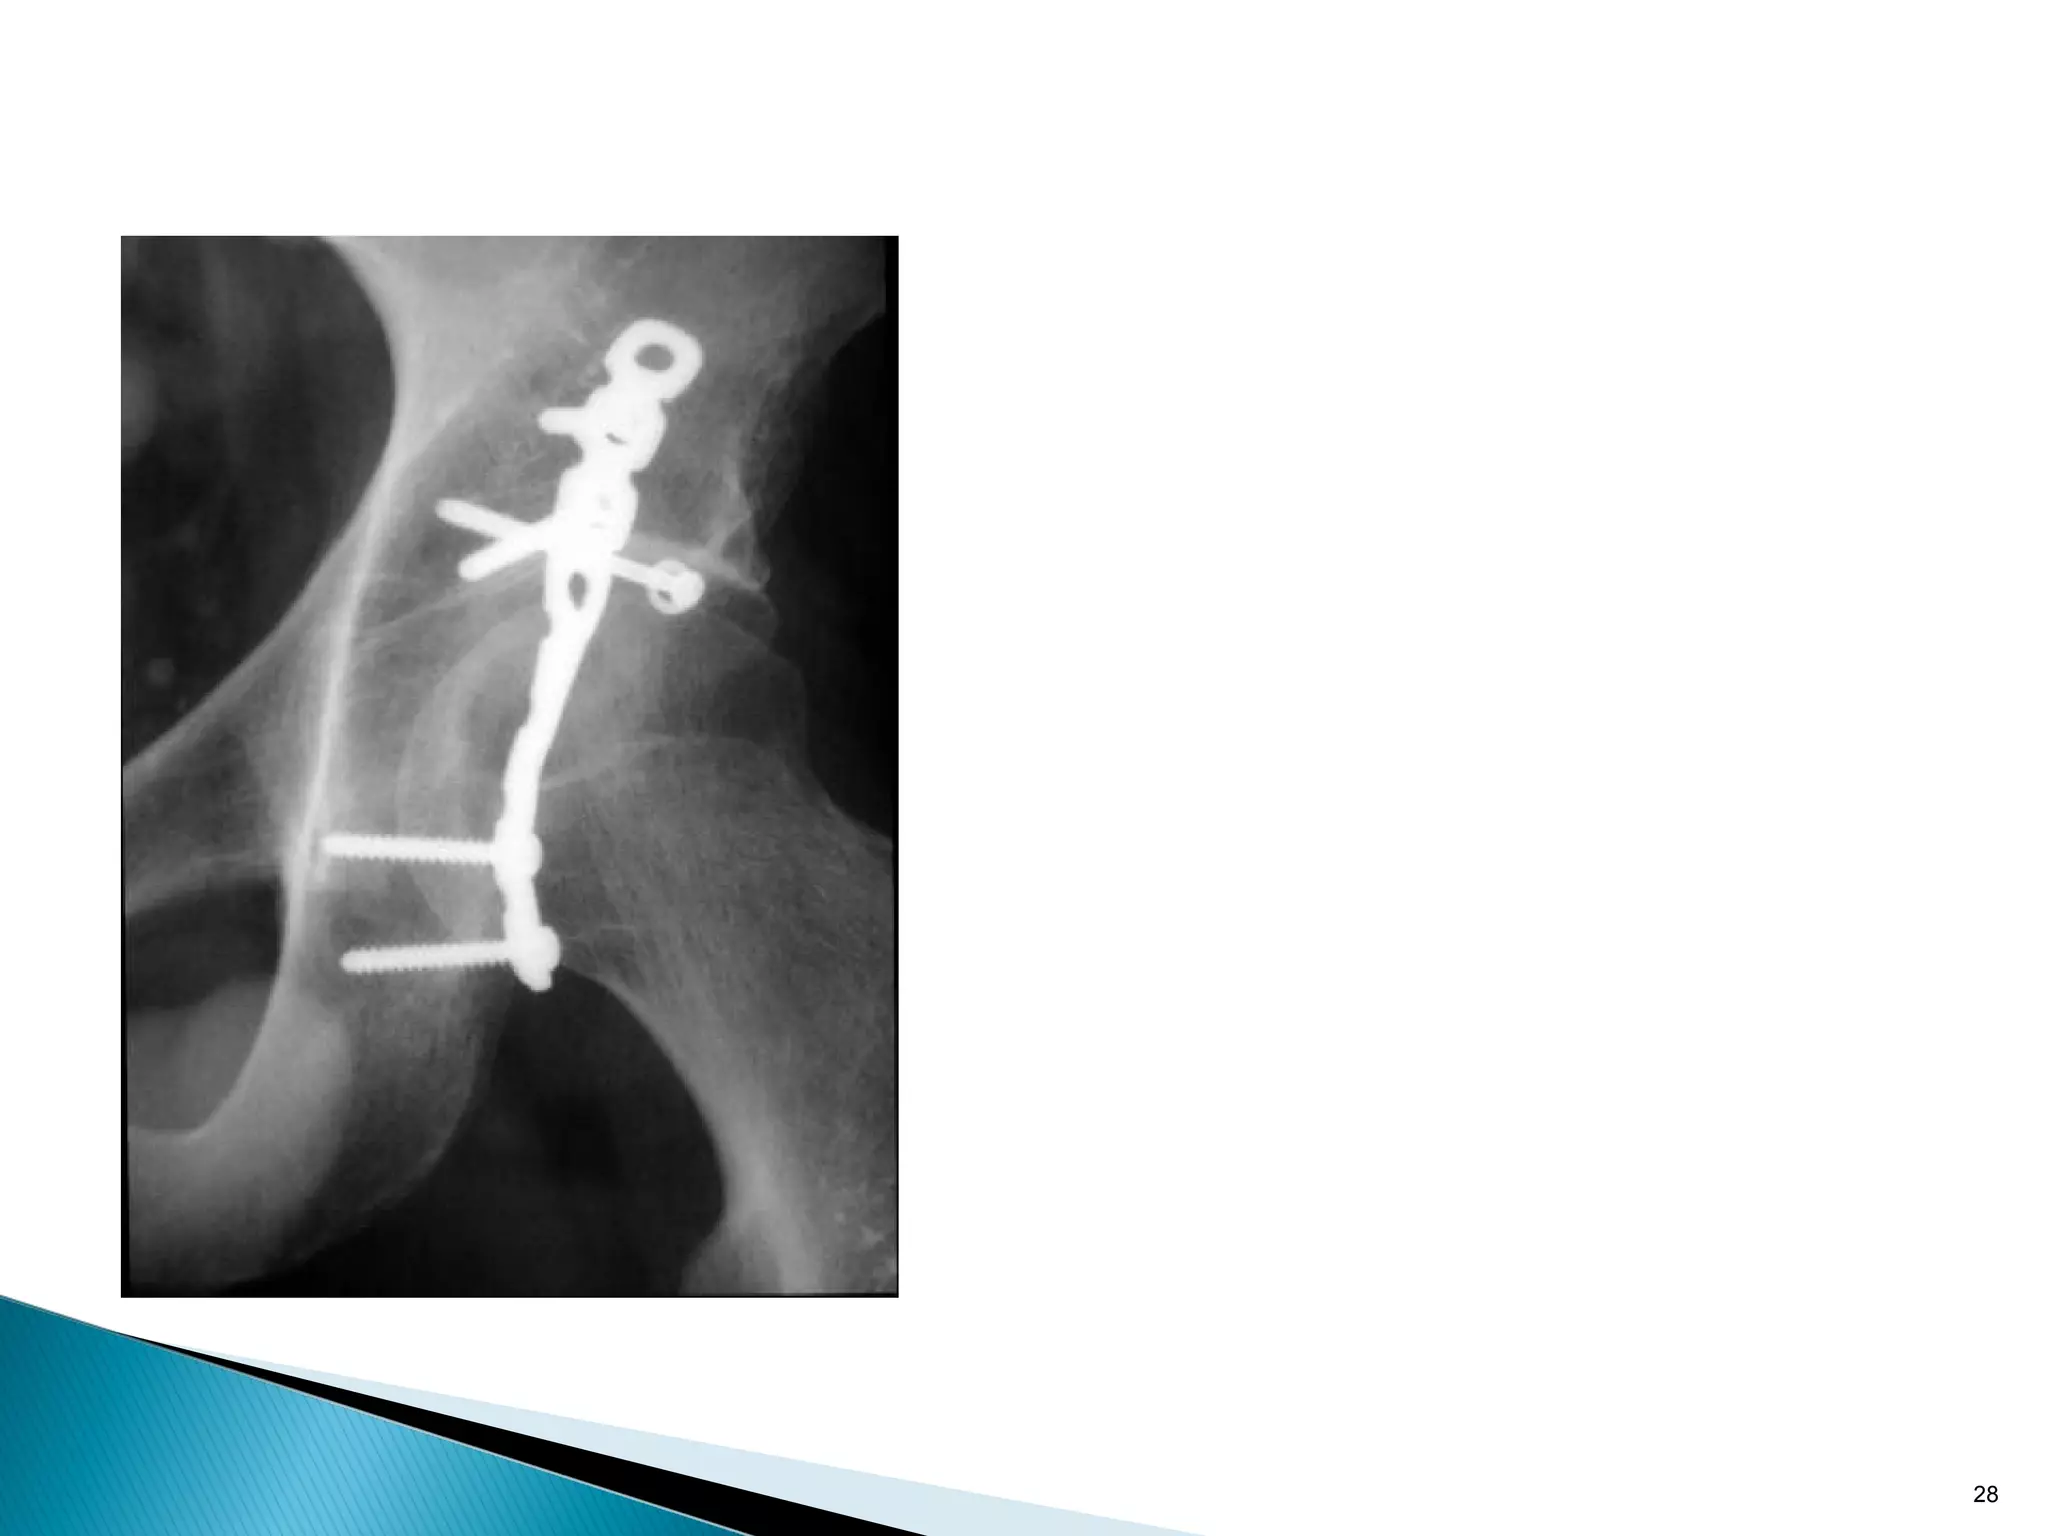

Absolute stability: tension band principle

In the eccentrically loaded femur the tension side is always

lateral.

A plate MUST be placed on convex (tension) side to counteract

distraction forces.

However there must also be a medial bony buttress, if

missing, the plate will break due to fatigue.

Plate on concave side distracts fracture

20 Absolute stability: tensionband principle In the eccentrically loaded femur the tension side is always lateral. A plate MUST be placed on convex (tension) side to counteract distraction forces. However there must also be a medial bony buttress, if missing, the plate will break due to fatigue.

21 Plate on concaveside distracts fracture Absolute stability: tension band principle